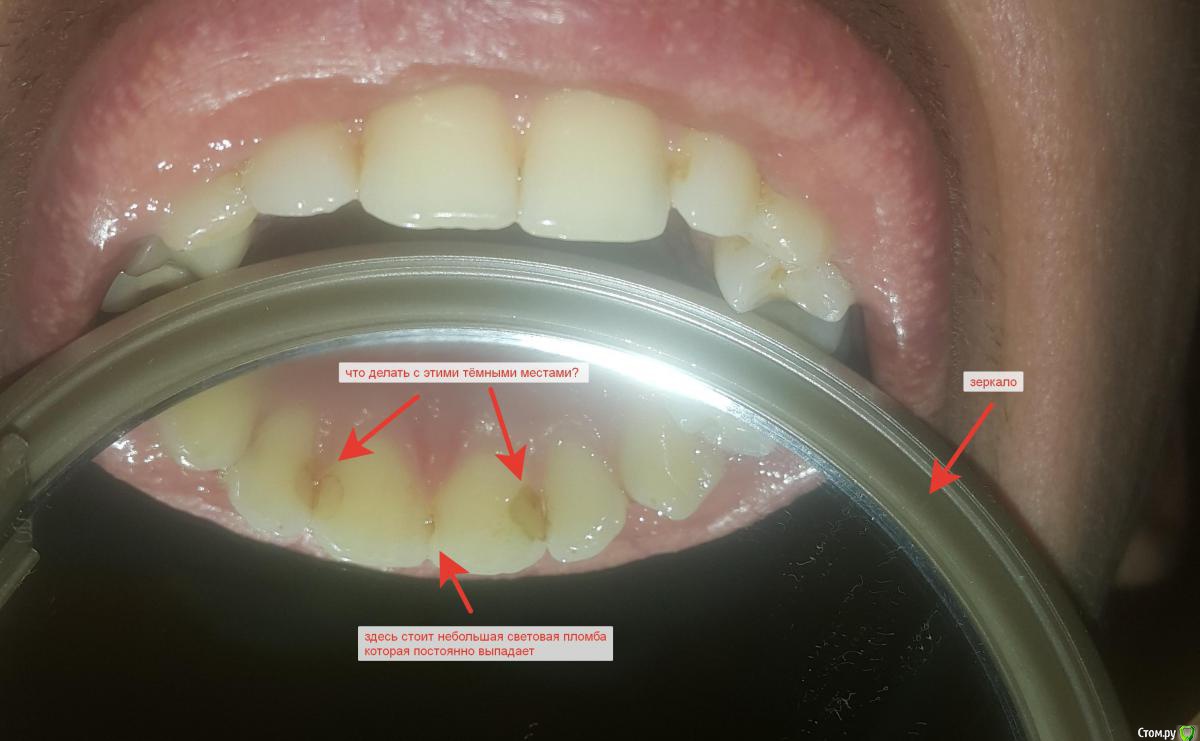

1) Сейчас мне 25 лет. Три года назад обнаружил, что между передними верхними зубами началось потемнение со внутренней стороны. Обратился к врачу. Врач сказал что это кариес, рассверлил, и установил пломбу. Надо отдать должное врачу, делал её очень медленно, около часа. Пломба держалась три года. Как только отвалилась, пошел в клинику уже к другому врачу. Мне опять туда поставили световую пломбу. Ставили очень быстро за минуть пять. Пломба отпала через два месяца. Пошел опять. Поставили повторно за минут пять. Когда обрабатывали место от предыдущей пломбы сказали «что всё было чисто», и поэтому не знают почему отвалилась так быстро пломба. Сказали, что если выпадет снова, то будут больше рассверливать зуб, чтобы пломба лучше установилась. Прошел месяц, и малюсенькая часть пломбы отвалилась. На фото это почти не видно, но видимо скоро опять отвалится полностью.

2) Кроме того, на зубах верхней челюсти с внутренней стороны опять началось потемнение (см. фото). Как я понимаю это кариес? Если да, то получается что единственный способ лечения это опять рассверливание? Стоит ли это делать? Обнаружил кстати эти тёмные пятна я сам( через зеркальце) несколько лет назад, врачи (в гос. клиниках) не предают этому значение.